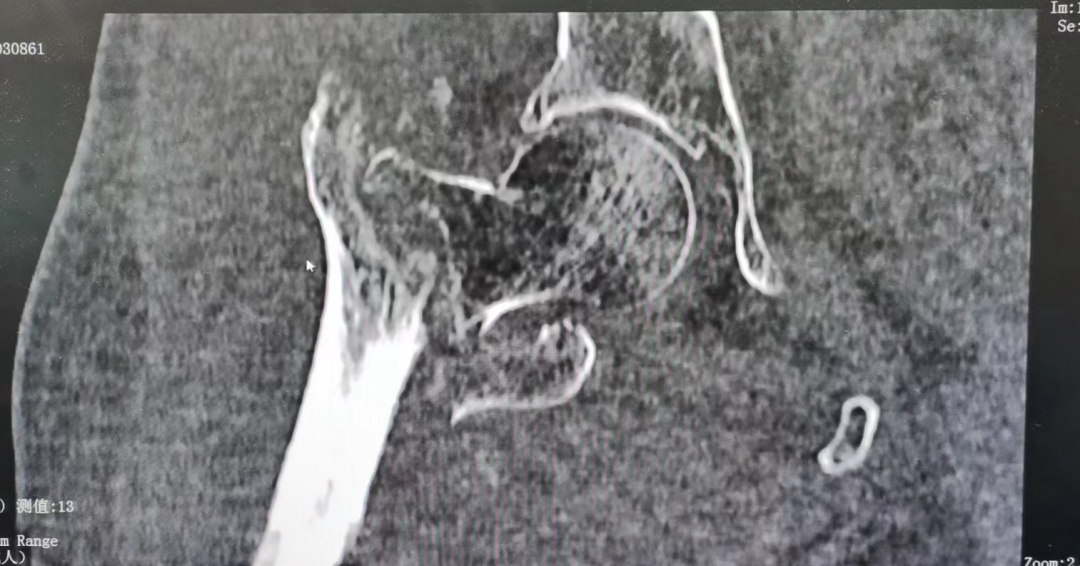

科室经过讨论后,最终选择行右股骨粗隆间骨折切开复位钢板螺丝钉内固定术,由于患者高龄及身体状况,手术对技术有一定要求。尽管手术难度大,但是经过术前的充分准备,完善相关的检查项目,外一科彭明主任团队精细的操作及麻醉医生、手术室护士的默契协作,手术取得了圆满成功。本次手术术程近一小时,采用小切口,微创技术,出血量仅60ml,手术成熟程度高

图片

(术后拍片)